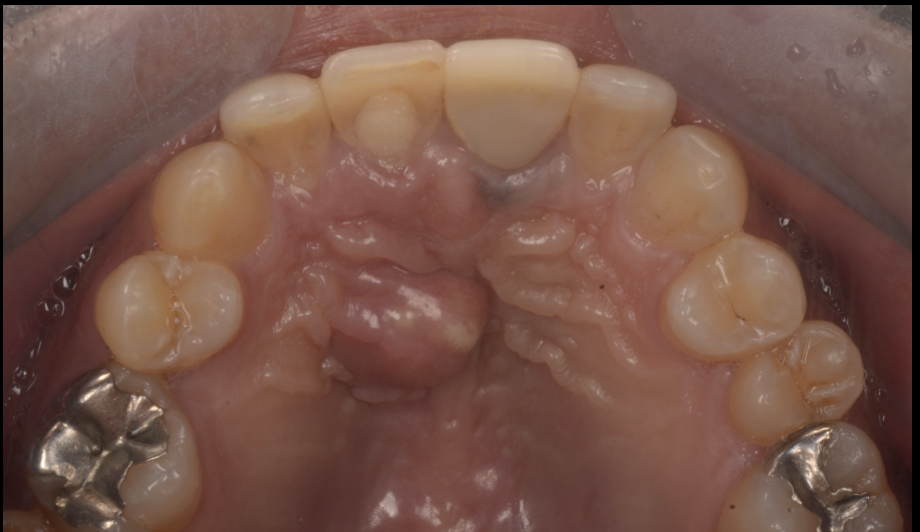

患者さんは以前から、近所の歯医者で腫れては根管治療を繰り返していた前歯がありました。

今回、再び痛みが出て受診したところ、これまでよりも強い痛みがあり、「この状態は厳しいので抜歯の方がいい」と説明を受けたそうです。

ただ、前歯を抜歯すると見た目だけでなく、顎の骨量(次の治療の土台)にも大きく影響します。さらに今回は、画像評価の中で切歯管嚢胞の併発が疑われ、単純に抜歯へ進むと

「骨を大きく失う」→「インプラントが難しくなる」

という負の連鎖になり得る状況でした。

今回の症例は、感染性病変(根尖性歯周炎)と、嚢胞性病変(切歯管嚢胞)が関係している可能性があり、治療の優先順位と手段を整理する必要がありました。

診断の要点|CT(CBCT)で「病変の正体と広がり」を立体的に評価

前歯部はレントゲンでは病変が重なって見えやすく、

「根の感染が主体なのか」

「嚢胞が主体なのか」

「両方が関与しているのか」

が判断しにくいことがあります。

当院ではCT(CBCT)で病変の範囲と位置関係を把握し、

根管治療で解決すべき領域と

外科的に対応すべき領域を分けて治療計画を作ります。